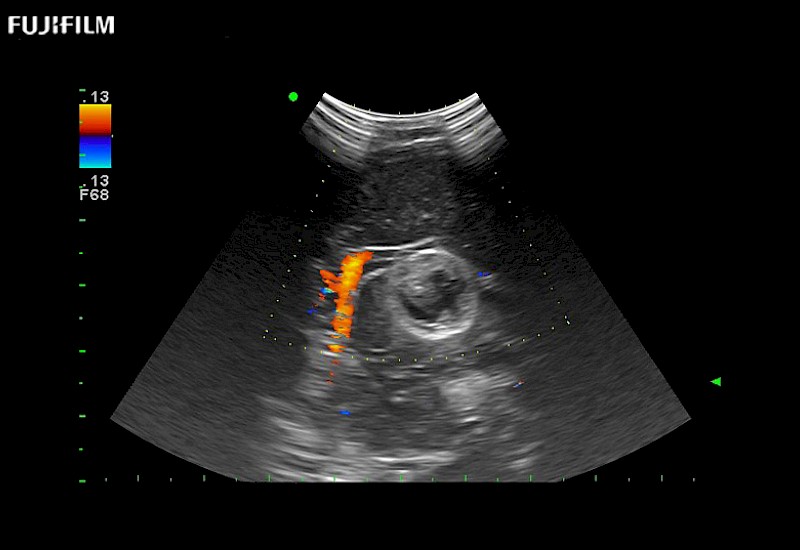

Exclusive 10mm side‐fire linear array transducer with 2.87mm diameter is ideal for real‐time visualization through and behind structures and instant, scalable definition of anatomy and vascularity including the ability to delineate and define tumor margins.

Main Specifications: